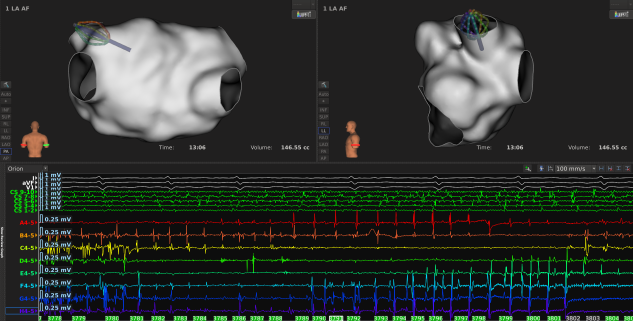

手术过程:

二:评估消融损伤方面

1

消融过程中LI稳定下降,通常5-8s到达平台期;

2

到达平台期后,最大LI下降值通常在15-25Ω范围内,提示消融有效;

3

消融过程中也要结合电位判断消融效果,通常阻抗下降至平台期后,MiFi微电极电位下降或消失明显,继续放电5s;

LI值还可以提示心肌的健康程度,低电压区及疤痕区组织,基础LI要明显低于健康心肌,仅比血池略高约5Ω,有时甚至会低于血池阻抗;消融过的心肌(二次贴靠)LI值较首次会更低,大概在90Ω左右;

6

LI快速大幅下降超过40Ω,可能提示“Pop”风险;

7

消融完成后,可结合超高密度标测Vmap,验证评估即刻消融损伤效果。